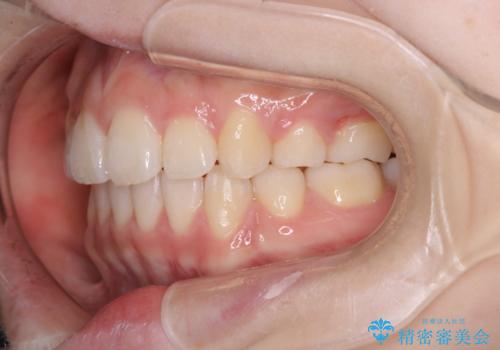

主訴のオープンバイトは改善し、抜歯をしたことで前歯が下がり綺麗になりました。抜歯矯正でしたが1年2か月という短い期間で終了しました。